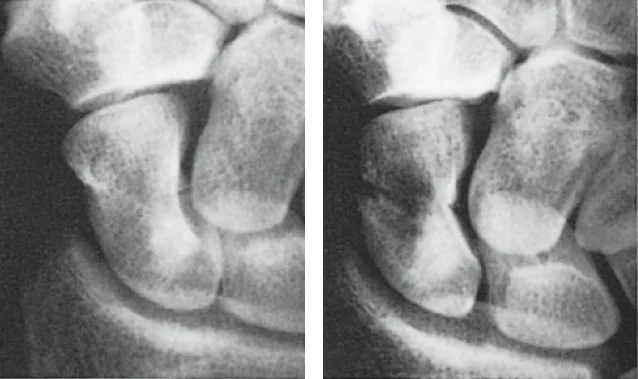

Imaging Principles

- Plain x-ray: (law of two’s)

- Two views: AP and Lateral

Law of Two’s

- Plain x-ray: (law of two s)

- Two joints: joint above and joint below

- To show other injuries

- To assess rotation

- Two limbs: for comparison

- more in children to compare epiphysis

- Two occasions

- e.g. stress fractures

- e.g. scaphoid fracture

- Two injuries

- e.g. patellar fracture and hip injury

- e.g. calcaneal fractures & spine injuries

- …and two Doctors!!

- Special views:

- Ankle mortis

- Calcaneal view

- Scaphoid views

- Shoulder dislocation: axial view

- Acetabular fractures: 45° tilt views

- Stress views

- Traction views

- Functional flexion/extension (spine)